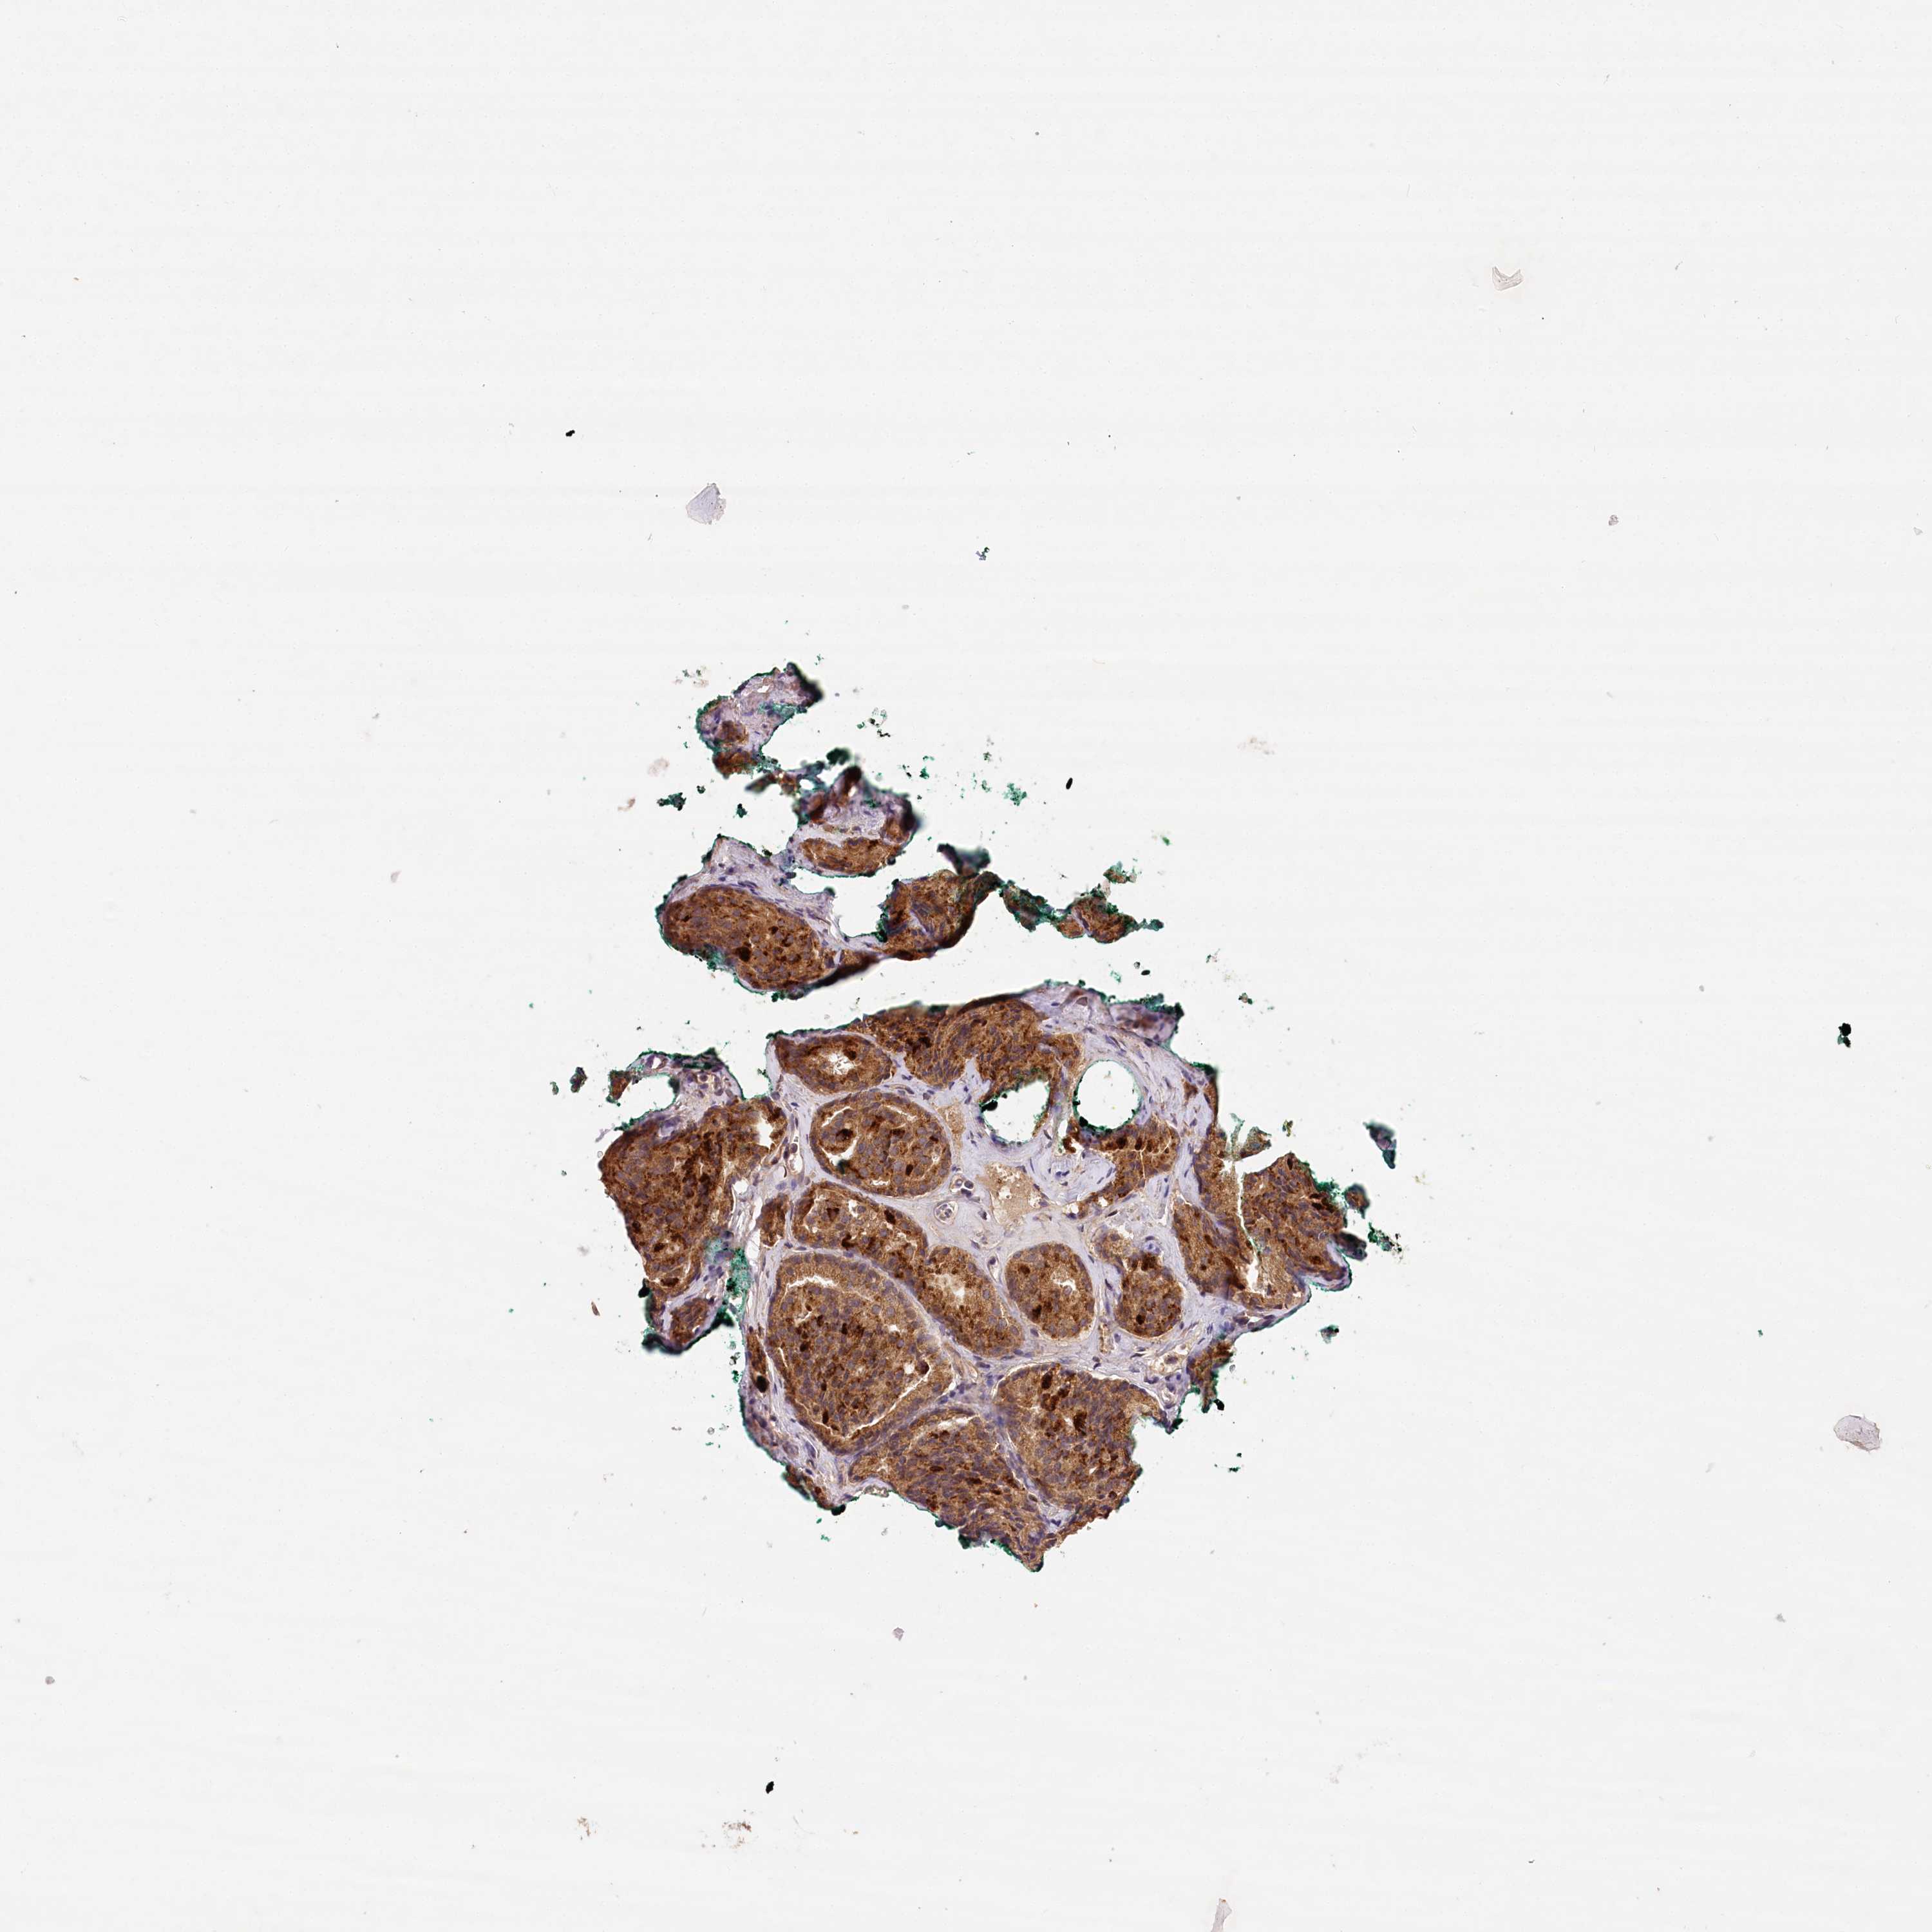

PROSTATE CANCER - Protein expressioni

A mouse-over function shows sample information and annotation data. Click on an image to view it in a full screen mode. Samples can be filtered based on level of antibody staining by selecting one or several of the following categories: high, medium, low and not detected. The assay and annotation is described here.

Antibody stainingi

Antibody staining in the annotated cell types in the current human tissue is reported as not detected, low, medium, or high, based on conventional immunohistochemistry profiling in selected tissues. This score is based on the combination of the staining intensity and fraction of stained cells.

Each image is clickable and will lead to virtual microscopy that enables deeper exploration of all samples and also displays staining intensity scores, fraction scores and subcellular localization as well as patient and tissue information for each sample.

Antibody HPA032060

Antibody HPA032062

Antibody CAB034116

Staining

High

Medium

Low

Not detected

Intensity

Strong

Moderate

Weak

Negative

Quantity

>75%

75%-25%

<25%

None

Location

Nuclear

Cytoplasmic/membranous

Cytoplasmic/membranous,nuclear

Adenocarcinoma, Low grade

Adenocarcinoma, High grade